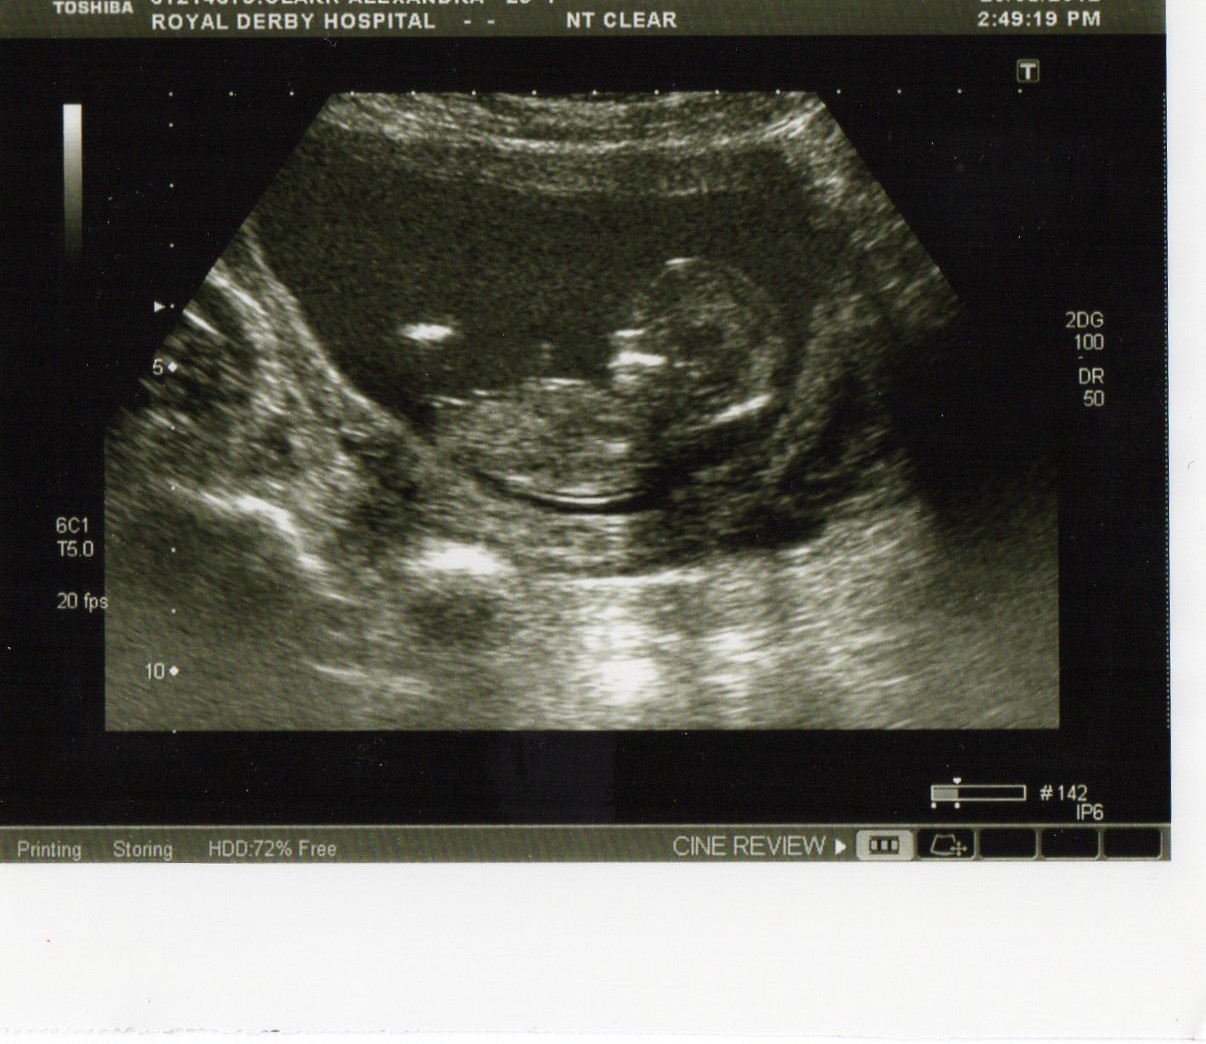

*WE DECIDED TO STAY TEAM GREEN AND NOW 7 DAYS UNTIL DUE DATE! ANY LAST GUESSES PLEASE?*

Please could you guess whether you think this is a boy or a girl? Baby is in a funny position so not sure if that affects the angle. Scan taken at 12 weeks 4 days.

Attachment 5101